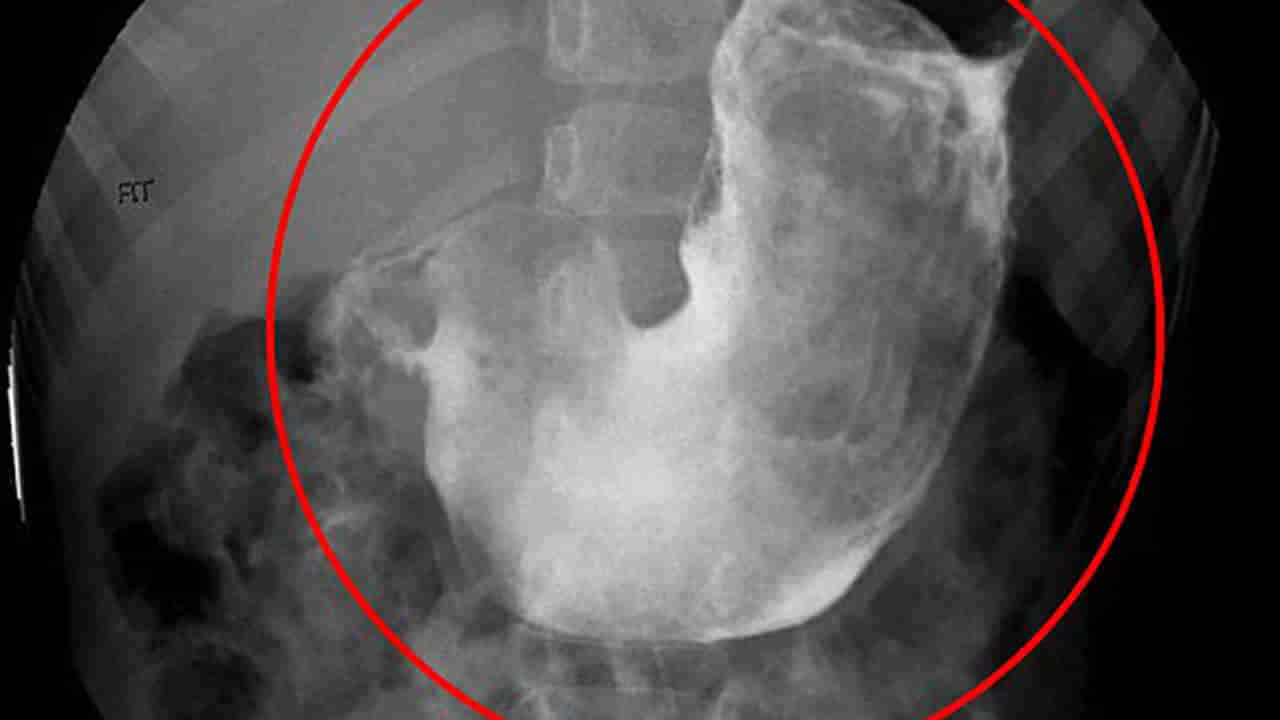

హిమాచల్ ప్రదేశ్లోని మండి జిల్లాలో వైద్యులు ఒక అరుదైన కేసును డీల్ చేశారు. ఒక మహిళ తీవ్రమైన కడుపు నొప్పి, నిరంతర వాంతులతో ఆసుపత్రికి వచ్చింది. ప్రాథమిక పరీక్షలు చేయగా.. కడుపులో ఏదో ఉందని గుర్తించారు. అల్ట్రాసౌండ్, సీటీ స్కాన్ వంటి పరీక్షల అనంతరం అది మానవ జుట్టుతో ఏర్పడి ఉండగా నిర్ధారించారు. ఈ సంఘటన మండీ జిల్లాలోని నేర్ చౌక్ మెడికల్ కాలేజీలో చోటుచేసుకుంది. బాధితురాలు మానసిక రుగ్మతలతో బాధపడుతూ, అనేక సంవత్సరాలుగా తన జుట్టును తానే తినటం వల్ల ఆ జుట్టు ఒక బాల్లా కడుపులో పేరుకుపోయింది. డాక్టర్ రాహుల్ మృగ్పురి, డాక్టర్ అజయ్ నేతృత్వంలో ఈ ఆపరేషన్ నిర్వహించారు. డాక్టర్ ష్యామ్లీ, డాక్టర్ పంకజ్.. నర్సింగ్ సిబ్బంది చంద్ర జ్యోతి, డింపుల్ లాంటి వారు ఈ సర్జరీలో కీలక భూమిక పోషించారు. ఆపరేషన్ విజయవంతమైందని.. ప్రస్తుతం బాధితురాలి పరిస్థితి నిలకడగా ఉందని వైద్యులు తెలిపారు.

ఈ అరుదైన పరిస్థితిని ట్రైకోబేజోర్ అని వైద్యులు పిలుస్తారు. ఇది చాలా అరుదుగా కనిపించే వ్యాధి. ఇందులో జుట్టు లేదా ఇతర జీర్ణించలేని పదార్థాలు కడుపులో చేరి పెద్ద బాల్ మాదిరిగా మారతాయి. సీనియర్ మెడికల్ సూపరింటెండెంట్ డాక్టర్ రాజనీష్ శర్మ ఈ కేసు అరుదైనదిగా పేర్కొన్నారు. మానసిక ఆరోగ్యం పట్ల సమాజంలో ఉన్న అవగాహన లోపమే ఇలాంటి సమస్యలకు దారితీస్తుందని వివరించారు.